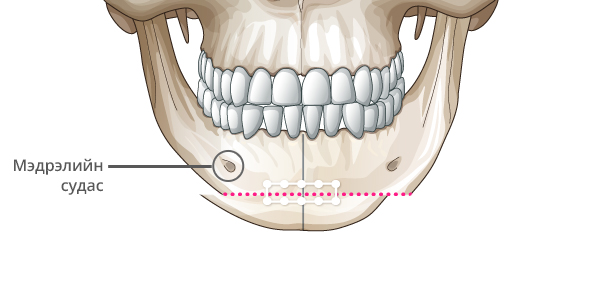

Step 3

Зүсэлт хийгдсэн эрүүний 2 талыг татаж нийлүүлнэ.